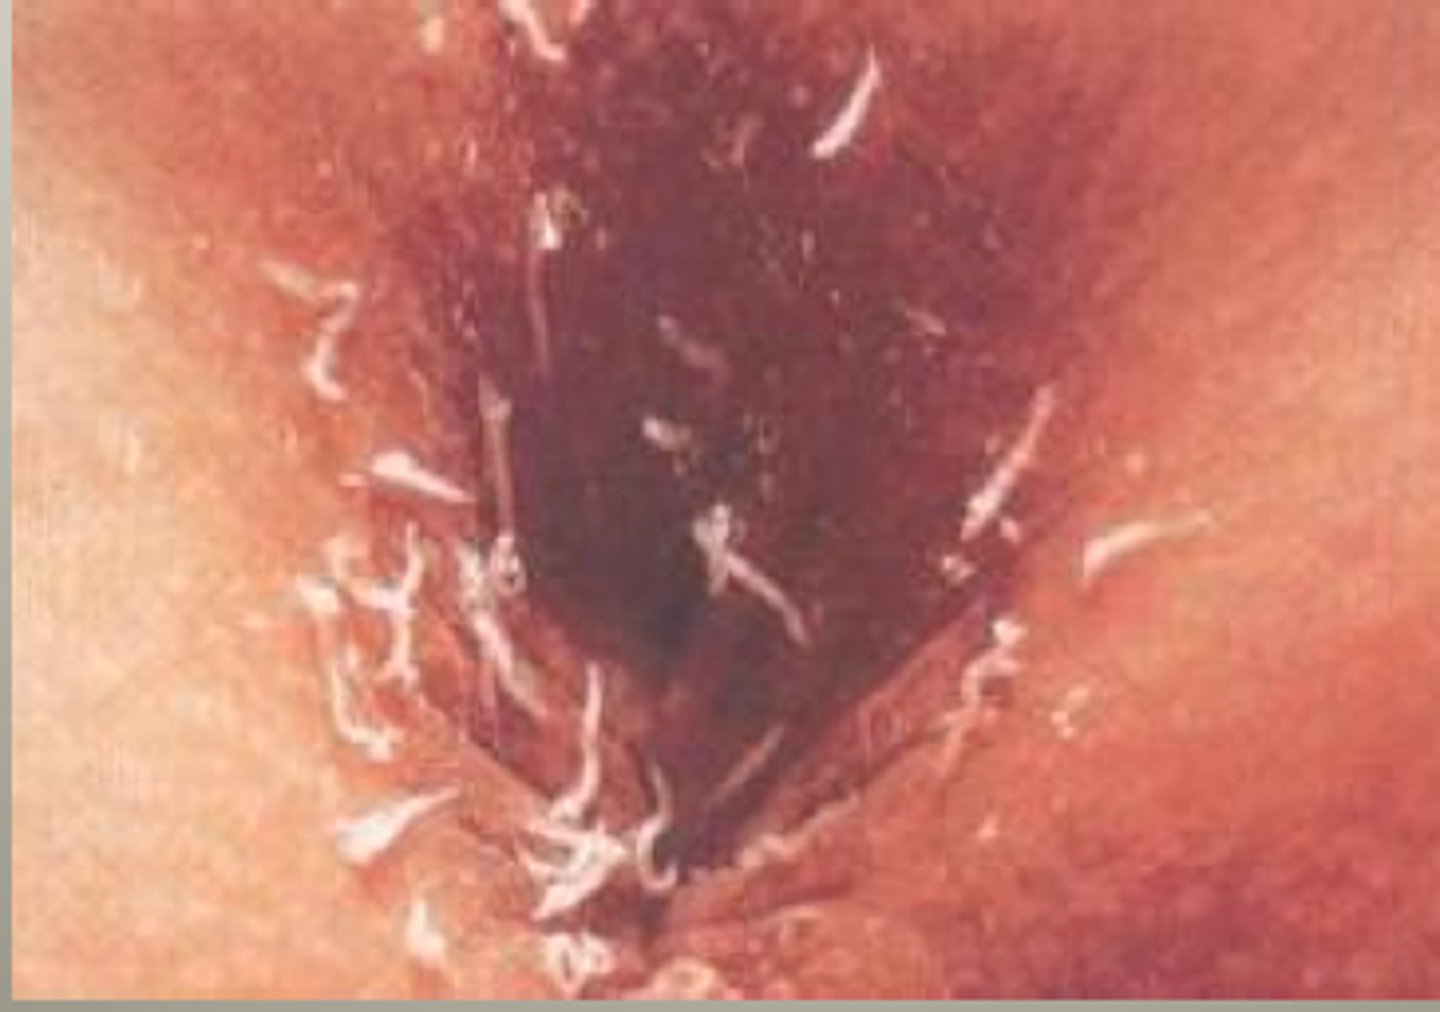

Pinworms

live in colon and cause intense nighttime anal itching

- diagnosed with tape test

Tx mebendazole